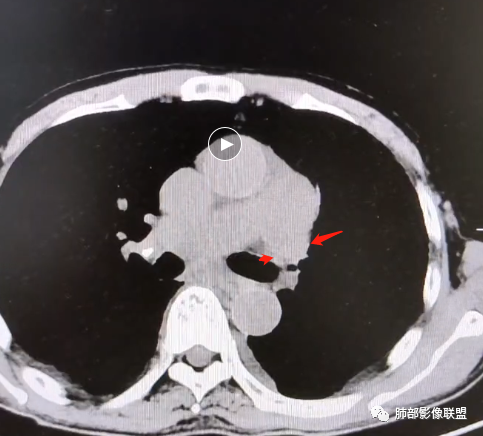

从肺动脉的主体分析:左肺动脉好像起始部就开始狭窄。

现在给的图像:是鼠尾状狭窄,而不会局部膨隆,远端细小那种。

现在的问题是自左肺动脉狭窄的原因:是急性栓塞?炎性病变?慢性血栓?

我想看看细节,局部肺动脉到底如何变化

4、肺动脉改变:左肺动脉起始部突然狭窄(右肺动脉代偿增大——继发肺内改变)

7.肺动脉主干扩张,左侧肺动脉主干见混杂密度影,上下肺动脉似不能连续追踪。

(增强:左肺动脉充盈缺损、闭塞)

5.影像左肺动脉栓塞、闭塞——上下肺动脉以远相对纤细——左肺动脉“断供”,且存在支气管动脉扩张可能。